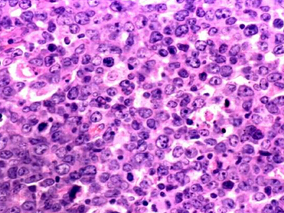

1小时条评论Elotuzumab,一种免疫单克隆抗体,靶向信号淋巴细胞激活分子家族成员7。在一项1bndash;2期研究中表明与来那度胺和地塞米松联合治疗复发或难治性多发性骨髓瘤患者具有活性。2015年8月,发表在《N Engl J Med》的一项3期研究证实,接受elotuzumab、来那度胺和地塞米松...